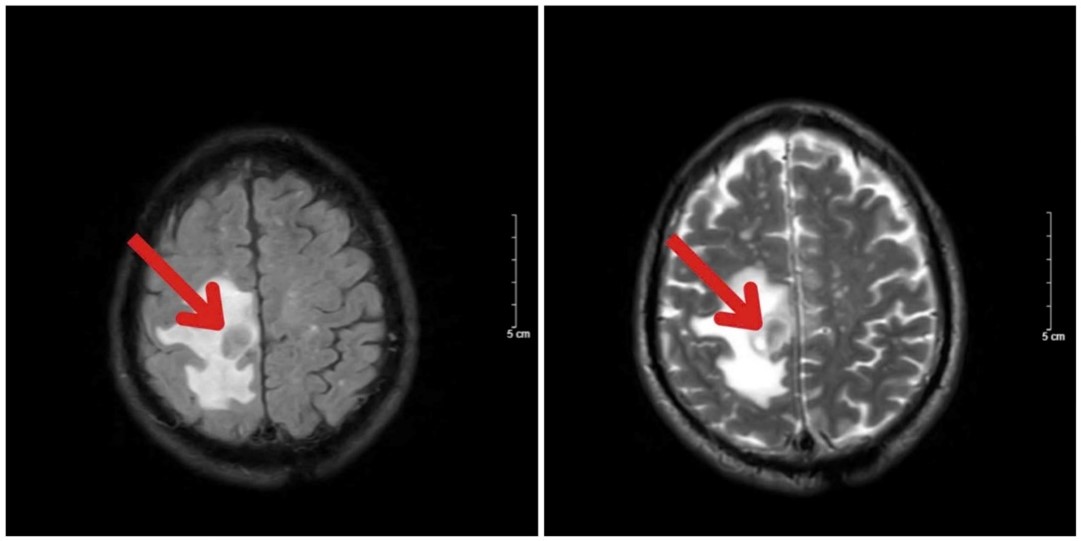

- Cộng hưởng từ sọ não: Thuỳ trán bên phải có tổn thương kích thước 18x18mm, bờ đều, ranh giới rõ, trong có thành phần hoại tử, ngấm thuốc đều dạng viền, kèm phù não rộng xung quanh.

Hình 2. Hình ảnh chụp cộng hưởng từ sọ não trước điều trị: Khối u thuỳ trán phải (mũi tên đỏ) kích thước 18x18mm kèm phù não rộng xung quanh